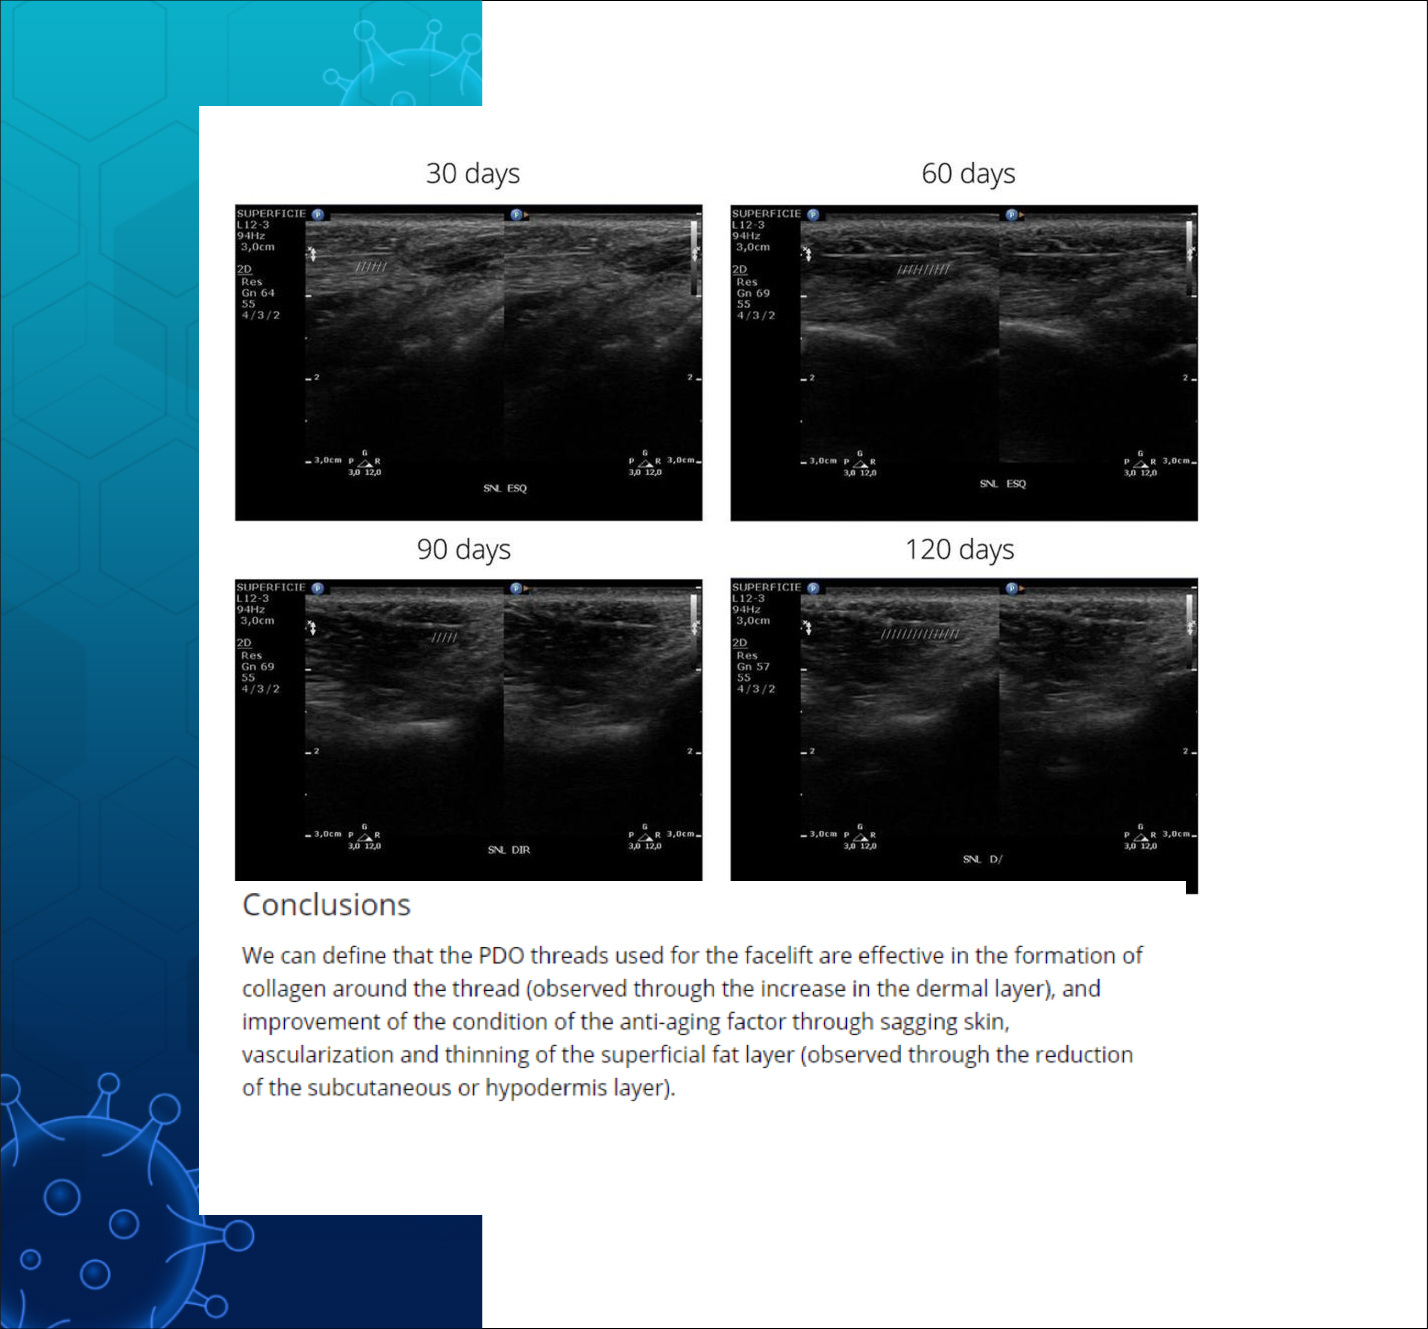

PDO실은 진피층의 두께는 증가시키고

(피부 탄력 증가)

혈관 형성을 촉진하며

콜라겐 형성을 촉진하고

피하지방층의 감소도 유발하는것으로

실험 대상 모두에게서

초음파 검사를 통해 관찰 되었다.